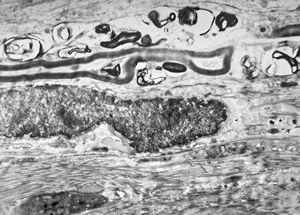

M,13y. | n. suralis - hypertrophic demyelinating neuropathy

F,31y. | hypertrophic demyelinating neuropathy - n.suralis

F,13y. | F,13y. | n.suralis … axonal neuropathy … Charcot-Marie-Tooth disease